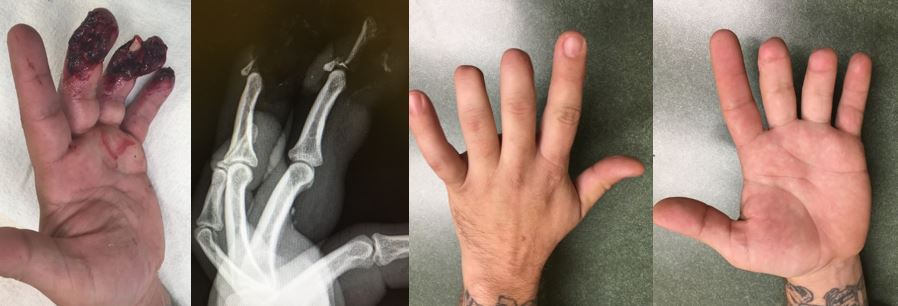

Dr. Franko performs a high volume of fingertip injuries related to motor vehicle accidents, motorcycle accidents, table saws, crush injuries, car doors, and more. Injuries includes open fractures, avulsions, amputation, nail plate loss, nail bed injuries, etc. He uses a variety of techniques including conservative wound care, simple suture repair, suture nail bed repair, dermabond (superglue) nail bed repair, V-to-Y flaps, Moberg flaps, first dorsal metacarpal island flaps, pin fixation, screw fixation, and revision amputation. The specific treatment best for you and your injury is based on each individual’s personal needs.

The following images highlight pre- and post-operative injuries and outcomes. For more details about these cases and others, check out Dr. Franko’s Patient Stories.

Before After